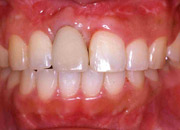

・CASE.2(下顎に 4 本のインプラントを埋入した症例)